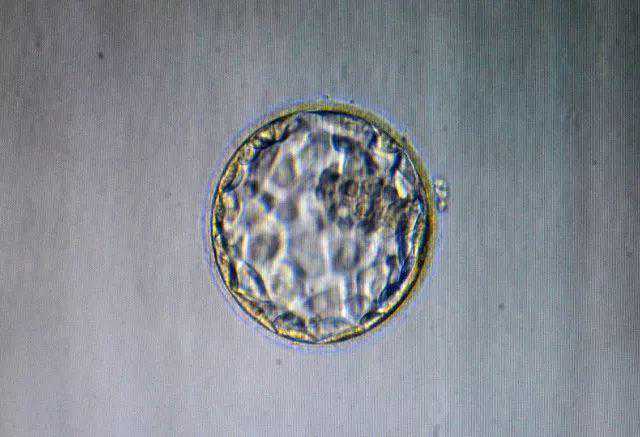

“你看他们发育得多好,多可爱!”舟山市妇幼保健院生殖医学中心副主任夏邦世指着电脑屏幕上的八细胞胚胎图片喃喃自语,言语中掩饰不住的喜悦。

授精后逐渐发育的受精卵。科学的解释是:精子进入卵细胞后,尾部消失,头部变圆膨大,形成雄原核;次级卵母细胞完成减数第二次分裂后,其细胞核形成雌原核。雄原核与雌原核接触,各自的核膜消失、联合,二性染色体在其后的合子分裂中混合、配对,受孕宣告结束,一个新生命宣告开始。